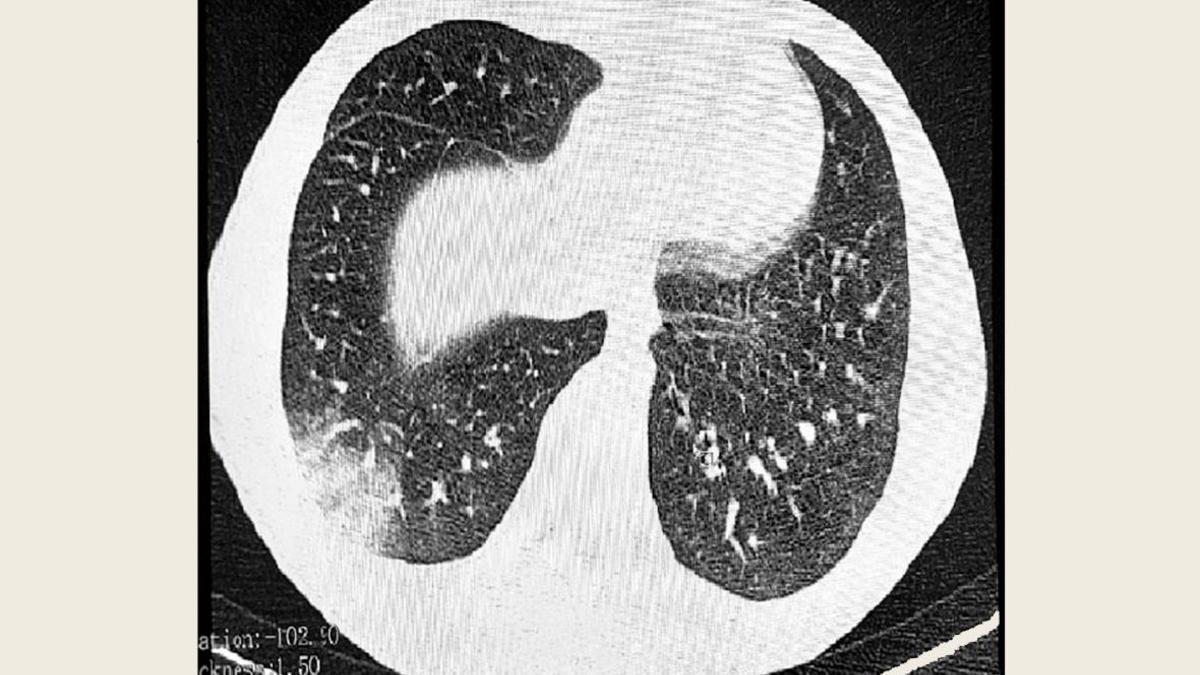

У одного из подростков в Томске врачи нашли новое опасное заболевание вейперов EVALI (е-cigarette and vaping use-associated lung injury), также называемую «попкорновой болезнью». Это один из первых случаев болезни, официально зафиксированных в России, говорится в Telegram-канале регионального управления Роспотребнадзора.

Болезнь представляет собой новую форму бронхита и проявляется в виде воспаления, образования рубцов и сужения бронхиол. Ее название связано с тем, что при прослушивании легких пациента врачи слышат звуки, похожие на треск разрывающегося попкорна. Развивается заболевание из-за употребления курительных смесей, в составе которых присутствует ароматизатор диацетил, опасный при регулярном вдыхании через вейп.

Ранее в Минздраве говорили, что основными симптомами EVALI, как и у COVID-19, считаются высокая температура, общая слабость и недомогание, кашель и одышка. Одним из первых признаков EVALI является нарушение работы желудочно-кишечного тракта. Также происходят патологические изменения в легких курильщика, которые выявляются при помощи компьютерной томографии.